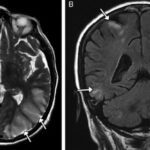

En la literatura se encontró caso de una mujer de 42 años, consumidora esporádica de MDMA, quien acudió a la guardia con síntomas de cefalea, alteración visual e hipertensión por síndrome de encefalopatía posterior reversible. Las imágenes radiológicas permitieron observar edema córtico-subcortical bilateral confluente de predominio parieto-occipital posterior. A partir de las imágenes radiológicas se pudo intervenir a través de un tratamiento con soporte y control de la presión arterial. (18) (ver Imagen 10).

En esta investigación que se viene señalando, se puede mencionar el caso de un joven de 16 años, con alteración aguda del estado mental por inhalación de vapor de heroína. Se le efectuó una RM que evidenció hiperintensidades en T2 de la sustancia blanca simétrica difusa infratentorial y supratentorial. El diagnóstico clínico en este caso fue rabdomiólisis, que afecta predominantemente la musculatura posterior del cuello(21) (ver Imágenes 11 y 12).

Otro caso que merece ser comentado es el de un adolescente de 15 años que presentó encefalopatía y signos extrapiramidales por ingestión de metadona. La RM evidenció focos de infartos agudos en el caudado y putamen, así como infartos corticales de la línea divisoria de aguas parietales(21) (ver Imagen 13).